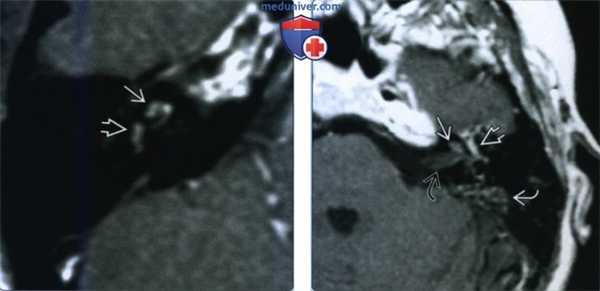

(Слева) При аксиальной МРТ Т1 ВИ С+ FS у годовалого мальчика с перенесенным менингитом и нейросенсорной тугоухостью определяется патологическое контрастирование базального завитка улитки с обеих сторон, сопоставимое с менингогенным лабиринтитом.

(Справа) При аксиальной МРТ Т2 ВИ FSE у пациента с двухсторонним лабиринтитом определяется гиперинтенсивная жидкость (норма) в улитке с обеих сторон. Наличие жидкости с типичным или слегка гипоинтенсивным сигналом позволяет отличить лабиринтит от объемного образования.

(Слева) При аксиальной МРТ Т1 ВИ С+ у пациента с внезапно возникшим головокружением и тугоухостью на фоне вирусного лабиринтита определяется патологическое контрастное усиление завитков улитки и преддверия.

(Справа) При аксиальной МРТ Т1 ВИ С+ определяется контрастирование улитки и внутреннего слухового канала у пациента с двухсторонним отомастоидитом, оталгией, параличом ЧН VII и тугоухостью. Барабанный сегмент ЧН VII в этом примере тимпаногенного лабиринтита также утолщен и накапливает контраст.